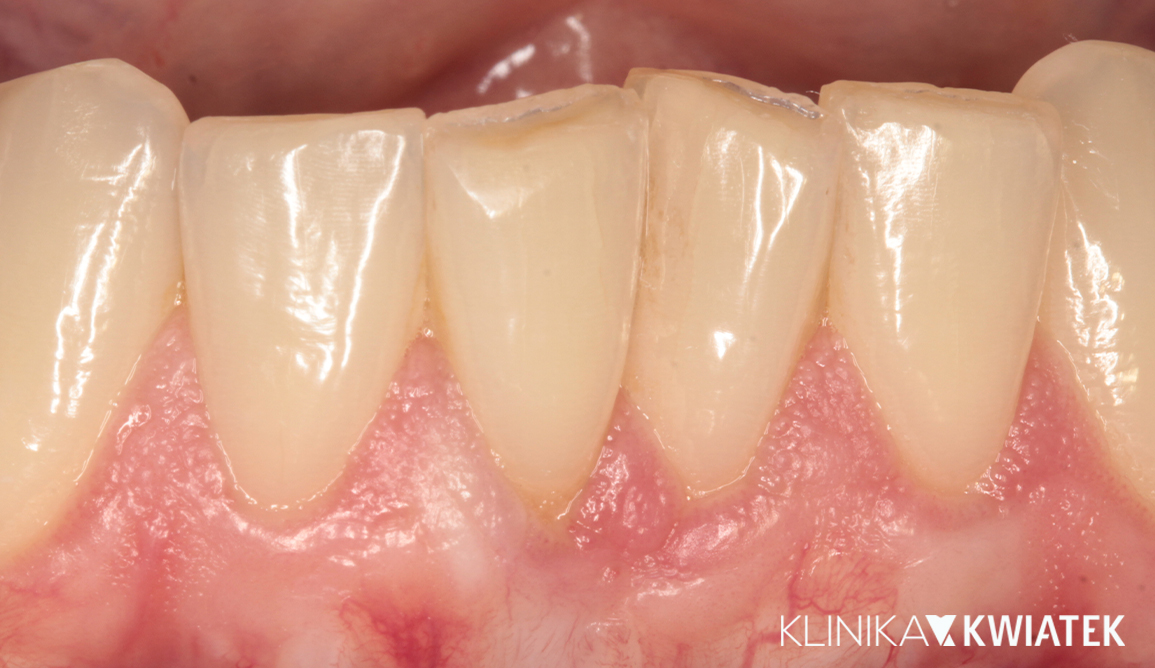

PRZED

Pan Jakub zgłosił się do kliniki z wadą zgryzu oraz licznymi problemami wynikającymi z nieprawidłowego ustawienia zębów. Leczenie wymagało współpracy specjalistów z kilku dziedzin stomatologii, precyzyjnego planowania oraz konsekwentnej realizacji kolejnych etapów terapii.

Dzięki ogromnej determinacji Pacjenta, który pomimo dużej odległości regularnie przyjeżdżał na zaplanowane wizyty, możliwe było przeprowadzenie kompleksowego leczenia, którego efektem jest doskonale zbalansowany zgryz oraz spektakularna i w pełni naturalna metamorfoza uśmiechu.